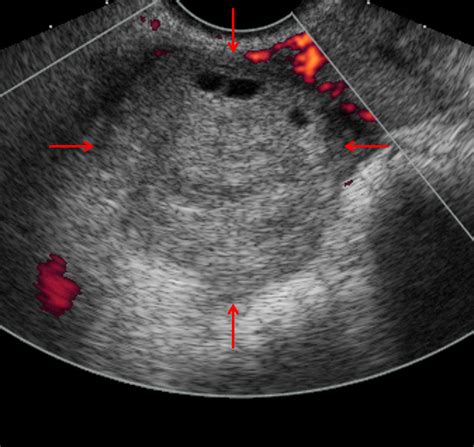

Abnormal Blood Flow Patterns

While the absence of flow is the most definitive sign, it is also a late finding. Radiologists look for subtle changes, such as high-resistance flow in the ovarian artery, which suggests the ovary is struggling to receive blood against the pressure of the twist. The presence of a “whirlpool sign”—a twisting of the vascular pedicle—is highly specific for torsion, though it can be technically difficult to visualize.